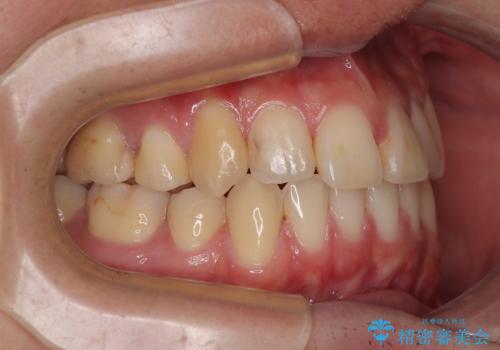

- 高校生の時に行った抜歯矯正の後戻りを気にして来院された患者様です。

インビザラインでの治療を希望されていて、デコボコの程度が中等度であり、安価なパッケージにて対応可能と判断されたため、インビザライン・モデレートを用いて矯正治療を行うこととしました。